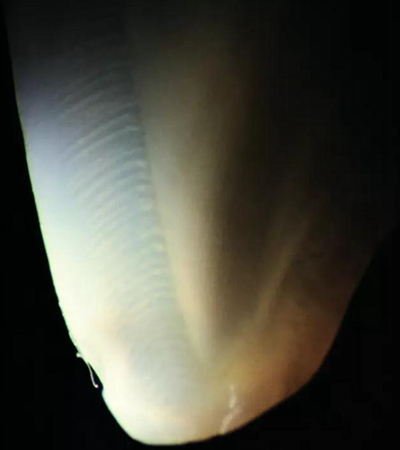

圖2.40顯微鏡下查看天然牙齒切片透照:

白色的(釉柱間質(zhì))和天藍(lán)色的(釉柱)薄層非常明顯。